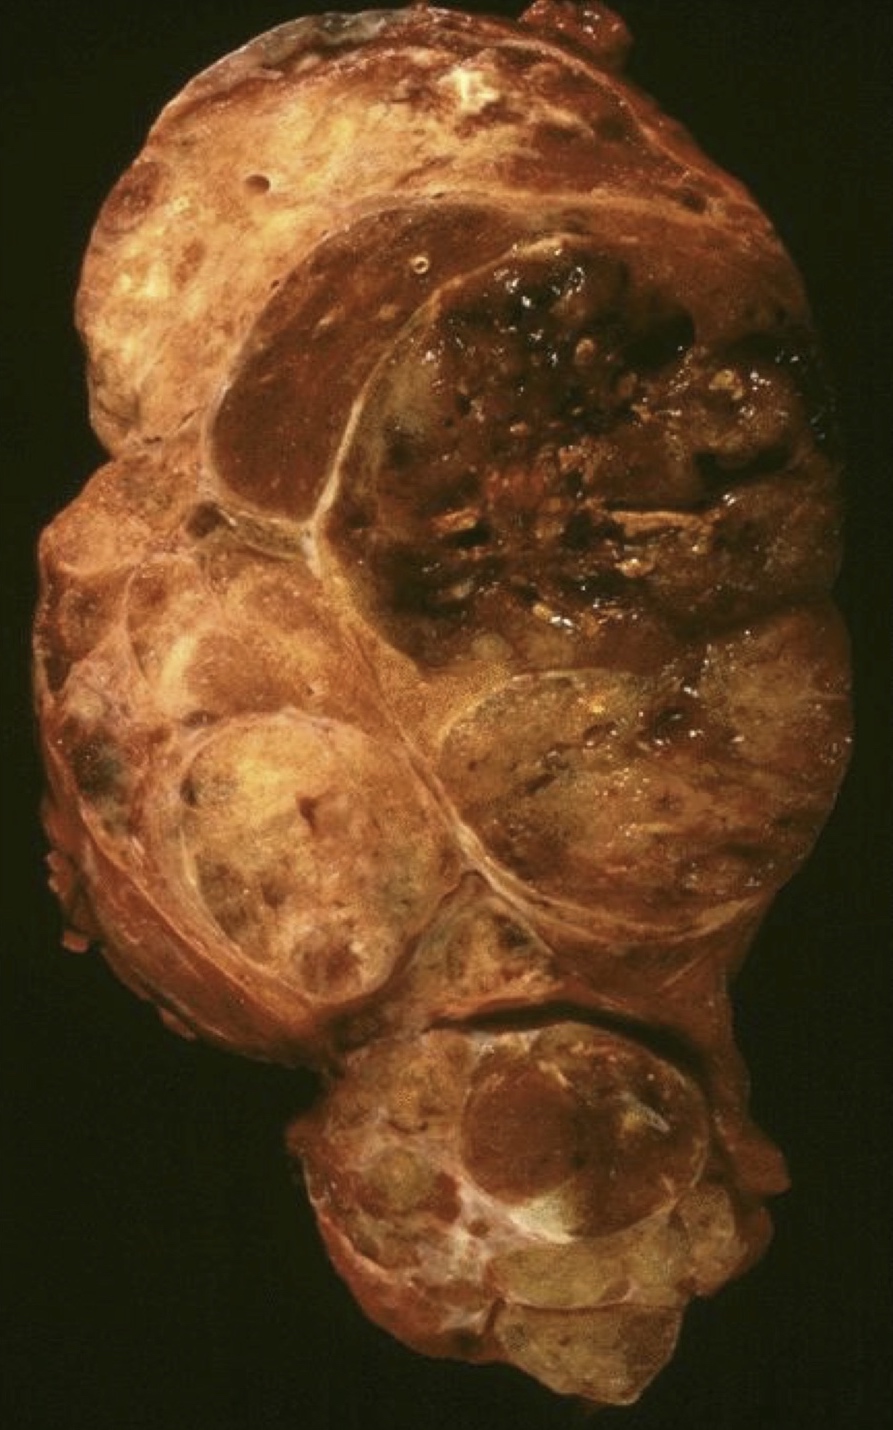

Gross description

- Simple goiters are usually firm with amber cut surface

- Multinodular goiters are asymmetric, large, 200 - 700 g (up to 2 kg)

- Increased size: lobe 8 - 15 cm, dominant nodules up to 10 cm

- Nodular and bumpy outer surface and variegated cut surface, cystic and hemorrhagic with brown gelatinous colloid nodules with focal calcification

- Reference: Diagn Cytopathol 2007;35:579